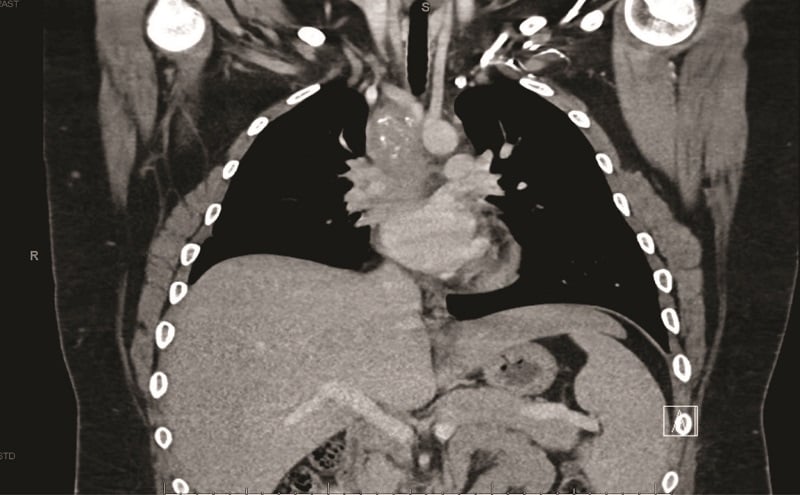

A contrast-enhanced computed tomography (CT) scan of the chest revealed a confluent calcified tissue density mass surrounding the subcarinal, right peritracheal, and anterior mediastinal region, causing significant extrinsic compression of the mid and distal trachea and right main stem bronchus, narrowing of the pulmonary artery, and partial encasement of the azygos vein.

CT of the chest with contrast showed a partially calcified soft tissue mass in the right paratracheal region, extending around the inferior trachea, carina, and proximal mainstem bronchi. The mass measured approximately 8.1 x 6.2 x 7.6 cm.